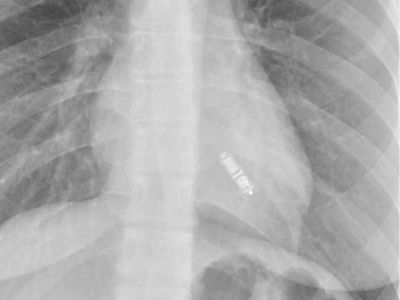

Leadless Pacemaker (Micra / Aveir)

A leadless pacemaker like Micra or Aveir is a tiny, self-contained device placed directly inside the heart to treat slow heart rhythms. It works without wires or a surgical pocket, lowering infection risks and recovery time. This modern design offers steady pacing, better comfort, and a simpler, safer experience for patients. You may opt for this treatment when-

The leadless pacemaker procedure is performed through a small vein in the leg. The device is guided into the heart and placed securely inside, avoiding chest cuts or wire placements.